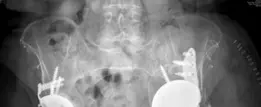

الأشعة السينية (Radiographs)

الأشعة السينية الأمامية الخلفية للحوض (AP Pelvis):

تُظهر هجرة مكون الحُق (عادةً للأعلى والداخل)، خطوط التخلخل حول المكون (مناطق سوداء تزيد عن 2 مم)، وتآكل العظم (Osteolysis).

- الأشعة السينية الجانبية للورك (Lateral Hip): توفر رؤية إضافية لهجرة المكون وفقدان العظم في المستوى الأمامي الخلفي.

في الحالة الموصوفة، أظهرت صور الأشعة المقطعية تلفًا شديدًا من النوع IIIB، مع فقدان كامل للقبة العلوية وتلف كبير في الأعمدة الأمامية والخلفية، مما يؤكد الحاجة إلى قفص الحُق التعويضي.